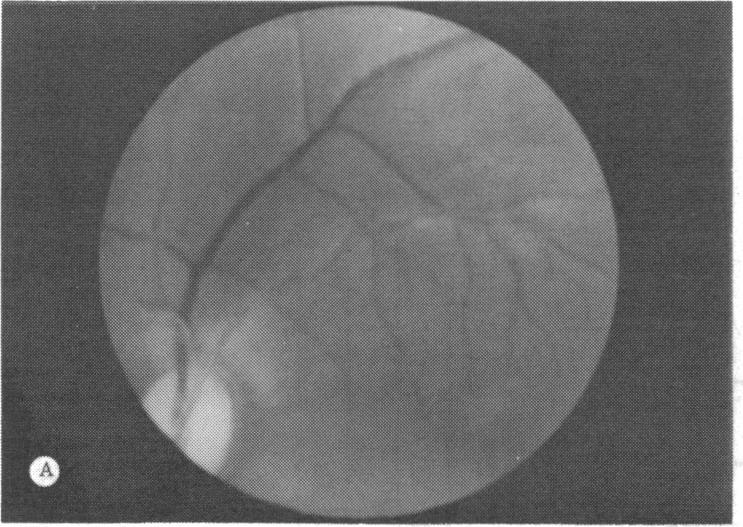

Panretinal photocoagulation as well as vitrectomy are the main treatment modalities for diabetic and other proliferative retinopathies. We show that both treatments introduce a new source of oxygen to the inner retina and propose that their efficacy in controlling the retinopathy results from their effect on the oxygenation of the inner retina. Panretinal photocoagulation reduces the oxygen consumption of the outer retina and allows more oxygen to diffuse to the inner retina from the choroid. Vitrectomy/lensectomy on the other hand allows aqueous humor to flow back to the retina and give oxygen to the inner retina which normally has a lower PO2 than aqueous humor. This causes the PO2 in aqueous humor to fall.

全视网膜光凝以及玻璃体切除术是糖尿病性和其他增殖性视网膜病变的主要治疗方式。我们发现这两种治疗方法都为视网膜内层引入了新的氧气来源,并提出它们在控制视网膜病变方面的疗效源于其对视网膜内层氧合作用的影响。全视网膜光凝减少了视网膜外层的氧消耗,使更多氧气从脉络膜扩散到视网膜内层。另一方面,玻璃体切除术/晶状体切除术使房水回流至视网膜,为通常PO2低于房水的视网膜内层提供氧气。这会导致房水中的PO2下降。